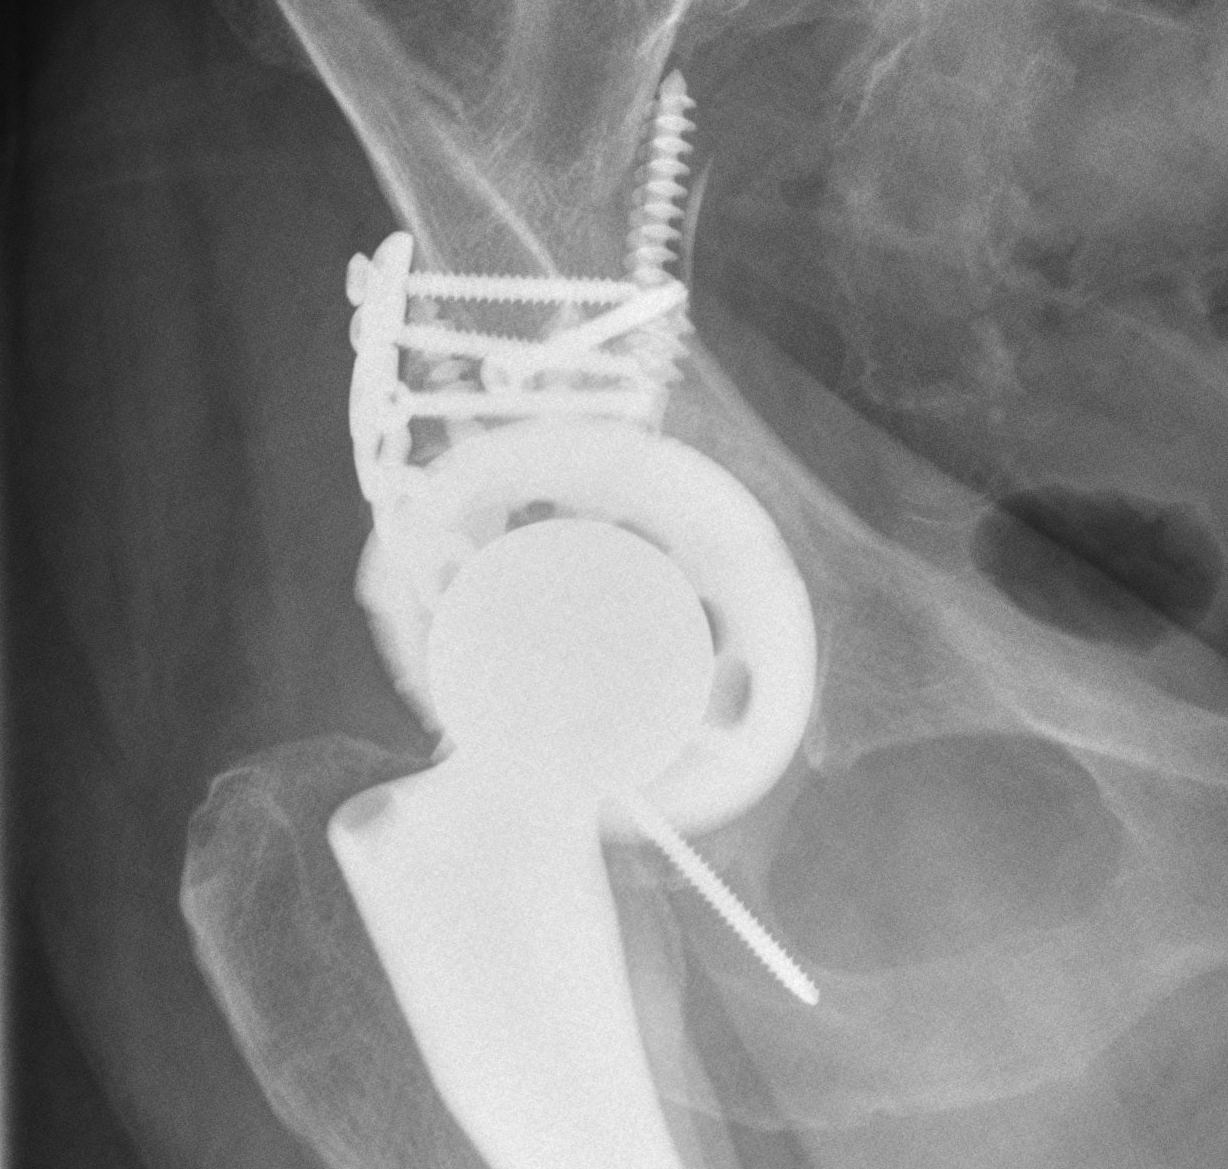

Intra-operative acetabular fracture

Postoperative acetabular fracture treated with double posterior plating